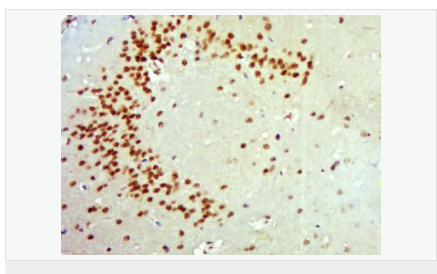

| 產品應用 | WB=1:500-2000 ELISA=1:5000-10000 IHC-P=1:100-500 IHC-F=1:100-500 ICC=1:100-500 IF=1:100-500 (石蠟切片需做抗原修復) not yet tested in other applications. optimal dilutions/concentrations should be determined by the end user. |

| 細胞定位 | 細胞核 分泌型蛋白 |